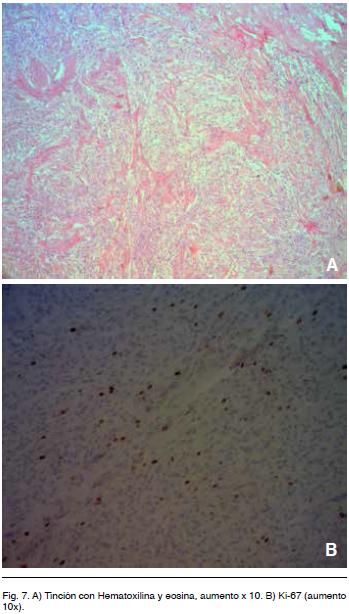

El informe histológico fue compatible con HPC, dada la elevada vascularización, por lo que se solicitó estudio inmunohistoquímico. El mismo fue negativo para CD34 pero positivo para factor VIII (de von Willebrand), presentando un índice de proliferación del 5-10%, por lo que se concluye que corresponde a un HPC grado III (OMS 2007).

Microscopía

Con respecto a la histología, los HPC son tumores compuestos por abundantes células fusiformes, grandes, con núcleos ovales y escaso citoplasma. Las células se disponen en torno a espacios vasculares de paredes delgadas (capilares y vénulas postcapilares) con un patrón característicos en “asta de ciervo” (Figura 7 A).

Existen HPC de la OMS grado II con 2 a 3 mitosis por 10 campos de alta potencia (HPF) y también se reportan más de 5 por 10 HPF como grado III. En la variante anaplásica (III OMS) también se puede encontrar necrosis, hemorragia y pleomorfismo nuclear4,8.

En cuanto a otros elementos de la inmunohistoquímica a tener en cuenta, Probst-Cousin y col. (b) encontraron que el grupo de pacientes con Ki-67 de < 5% tienden a sobrevivir más tiempo, sin embargo no predice con exactitud el resultado clínico8. Formalmete la OMS aún no acepta este hecho.